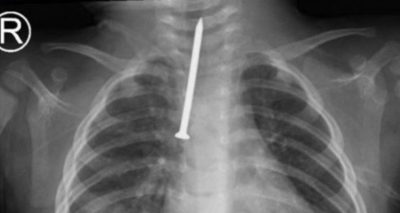

فريق طبي ينقذ رضيعاً ابتلع مسماراً بطول 5 سنتيمترات

أنقذ فريق طبي في مدينة الملك سعود الطبية حياة طفل رضيع يبلغ من العمر 8 أشهر، بعد إجراء عملية دقيقة لاستخراج مسمار من مجرى التنفس.وأجرى الفريق عملية تنظير صلب للقصبة الهوائية ومجرى...